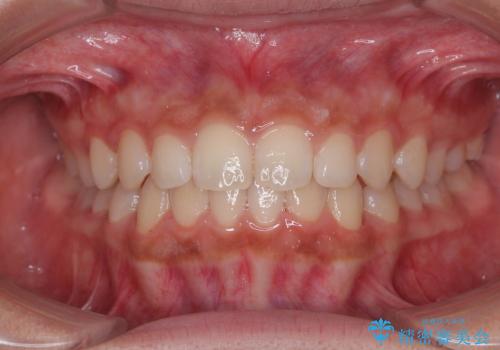

気になるすきっ歯を短期間で改善 インビザライン矯正

- 前歯の隙間を気にして来院された患者様です。

口元の突出感があり、小臼歯4本を抜歯して口元を引っ込める矯正治療も提案しましたが、本人は口元の突出感は気になっていないとのことで、インビザラインにて隙間やデコボコを改善することとしました。

軽度の歯列不正であったため、廉価版のインビザライン・モデレートパッケージにて治療を終えることができました。